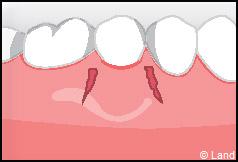

Outre la maladie parodontale, nous pouvons rencontrer des défauts de la gencive qui n’ont pas une origine infectieuse. Les plus fréquents de ces défauts sont les récessions gingivales, qui se traduisent par la migration de la gencive en direction de la racine (la racine est alors à nu).

Il existe plusieurs causes qui favorisent ce processus :

– une gencive fine ou des racines proéminentes

– un brossage trop agressif

– la plaque dentaire

– des couronnes mal ajustées.

Les conséquences de cette mise à nu de la racine dentaire sont multiples, le patient peut présenter une hypersensibilité dentaire et l’aspect de ces récessions peut être inesthétique. Dans ce cas, la chirurgie muco-gingivale est recommandée et elle peut se faire de différentes façons.